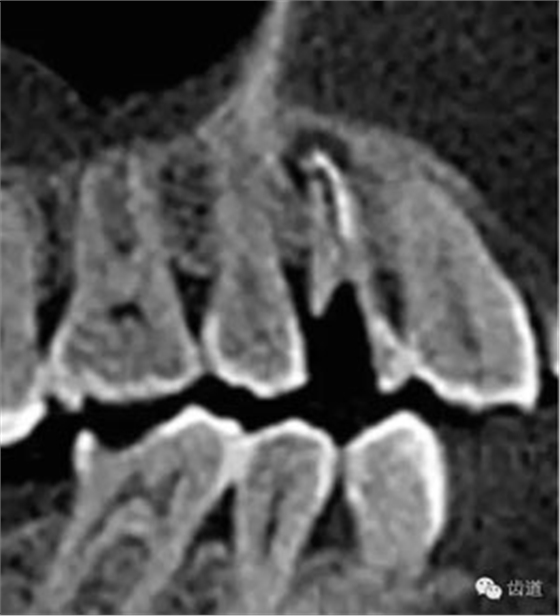

處理:1.建議CBCT檢查。

好的開始就是成功的一半。通過CBCT了解根管的位置,形態(tài),方向。

檢查顯示:近頰及腭根充填恰填,遠頰根管內(nèi)有少許充填物影像。根尖明顯低密度影像。